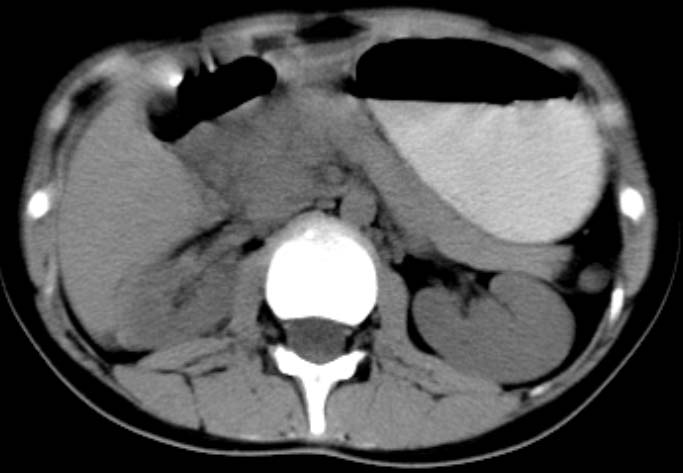

女,14岁。腹痛3天。腹部触诊未触及包块。碘剂阳性未增强。求助战友。。。。。。。。。。。

胰头部明显肿大,胰周间隙浸润,考虑胰腺炎可能性大

胰头部增大,周围模糊,有渗出,胰腺炎可能性大,建议结合化验检查;左侧输尿管上段略扩张.

胰头部明显肿大,胰头周脂肪密度加大。十二指肠环扩大受压。胰管未见确切扩张。考虑胰腺炎可能性大。建议增强扫描。

胰头部增大,周围结构模糊,并明显见渗出。支持:急性胰腺炎!

1)急性胰腺炎。2)肝右叶后上段肝内胆管结石。3)左侧输尿管上段扩张,原因待查。

胰头明显肿大呈肿物样,周围脂肪密度增高,结合病人年龄及临床表现,首先考虑炎性改变,建议结合实验室检查明确。必要是复查或mr检查

病灶应在胰头下区,不一定是胰头,结合周边低密度水肿,是否可能为十二指肠(xi)室炎症或其它炎症。

胰周无明显渗出,吉氏筋膜未见增厚。血尿试验室检查不支持。排除胰腺炎。